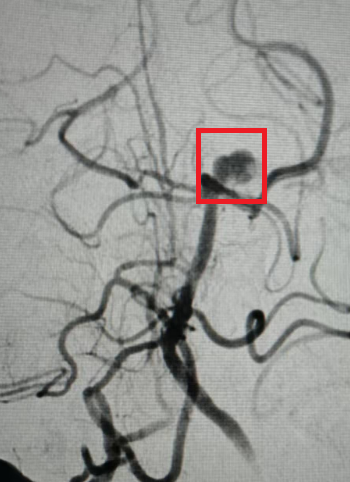

术前的动脉瘤。

由于王先生颅内动脉瘤破裂伴蛛网膜下腔出血,根据其动脉瘤形状、大小与周边血管位置关系等特点,医师团队决定使用新型自膨式动脉瘤瘤内栓塞系统(WEB)为其扫除颅内“炸弹”。针对此类基底动脉顶端部位复杂动脉瘤,相较于传统开颅及介入手术,应用WEB装置系统稳定性更高,能够明显降低手术并发症率,缩短手术时间,免除抗血小板药物治疗等优点。这种方式属于微创治疗手段,借助血管内介入的方式将特殊的栓塞材料送进动脉瘤内,阻断血液流入动脉瘤,从而以更小的创伤封堵动脉瘤,为患者的恢复创造更好的条件。据悉,团队这次使用了VIA17的输送系统,20分钟内成功将瘤内扰流装置植入动脉瘤瘤腔内,完美封堵瘤颈,即时造影可见动脉瘤不再显影。手术结束后王先生转入ICU继续进一步治疗。